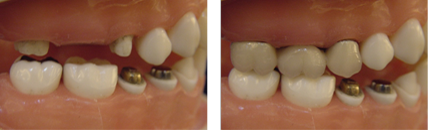

長牙橋導致蛀牙-案例一

拆下牙橋前

拆下牙橋後